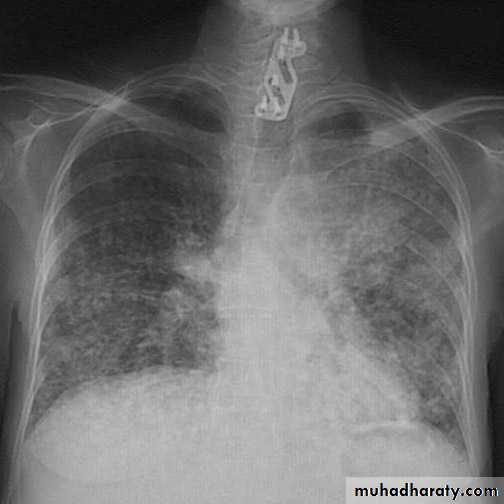

History and examinationRadiology

Miliary pattern (many small neoplasms)Cannon ball pattern (one large, spherical, well demarcated neoplasm).

Lymphangitis carcinomatosis (spread along lymphatics - white lines through lungs instead of black lines marking lymphatics.